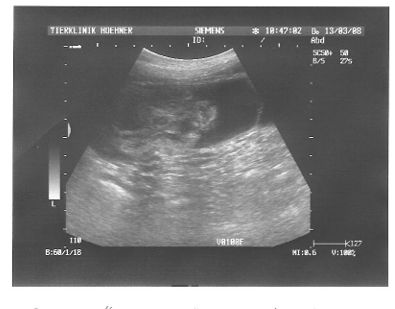

Ultraschallbild eines Embryo